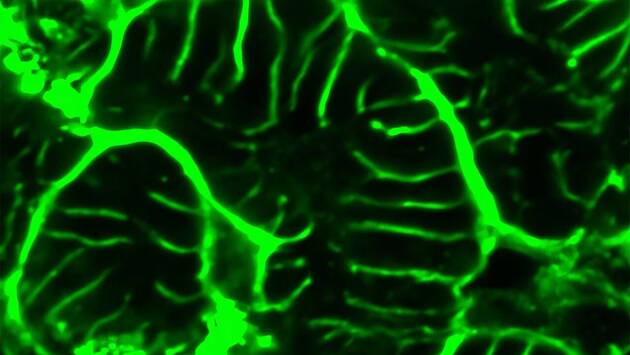

Белок cBIN1, вероятно, выступает в роли центрального регулятора клеточной структуры, координируя работу других белков, связанных с функцией сердечной мышцы. Улучшения были зафиксированы как на макроуровне, так и на микроскопическом уровне — клетки сердца стали лучше организованными.